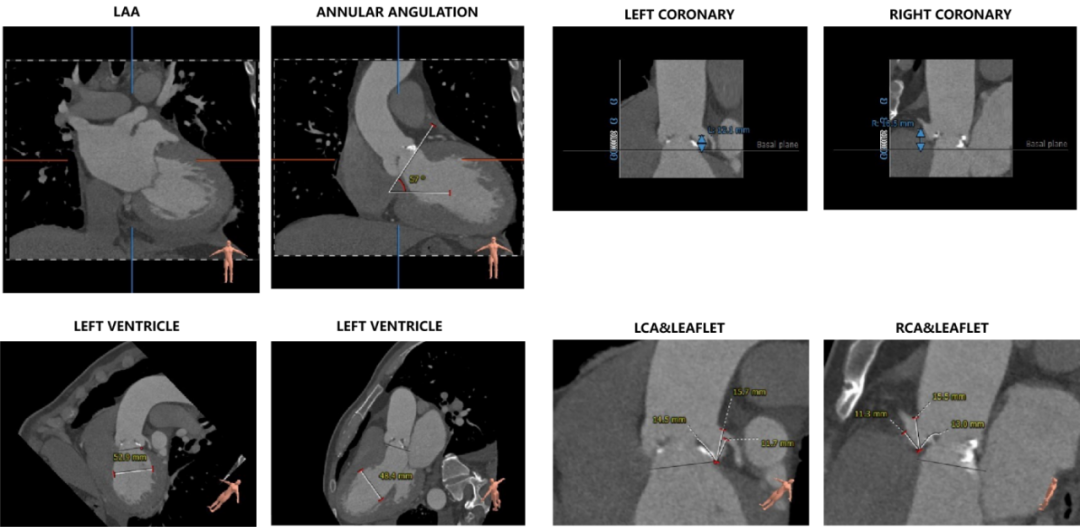

主动脉根部评估:

CT数据显示该患者为重度钙化的三叶式主动脉瓣,钙化分布集中于瓣叶边缘。

左冠开口高度12.1mm,右冠开口高度16.5mm,左侧冠脉预估存在一定遮挡风险;心室壁可见明显增厚。

①患者主动脉根部重度钙化,钙化灶分布集中,瓣膜位移风险较大。

②患者左室流出道周径较大,瓣膜释放后存在一定位移风险。

③患者瓣环水平夹角较大,近横位心,输送器过弓存在一定难度。

①患者为三叶式主动脉瓣,瓣环周径较大,左室流出道周径接近100mm,瓣膜锚定存在一定难度。

②患者瓣上限制性结构集中,须结合术中球扩谨慎选择瓣膜型号,降低因瓣膜压缩导致的位移风险。